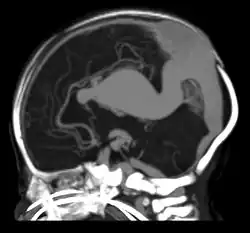

Falcine sinus

A falcine sinus is a venous channel that lies within the falx cerebri connecting the vein of Galen and the posterior part of superior sagittal sinus.[1] It is normally present during fetal development and involutes after birth. The presence of a falcine sinus has been associated with a vein of Galen malformation and other vascular anomalies. The persistence of a falcine sinus after the neonatal period was previously thought to be rare, but has recently been described to be present in up to 5% of all people,[2][1] appearings in approximately 2.1% of CT examinations of adult patients. Some authors have studied the plexus rather than the sinus, a rare form of the venous pathway between the layers of the cerebral falx, which connects the superior sagittal sinus with the inferior sagittal sinus and the straight sinus.[3]